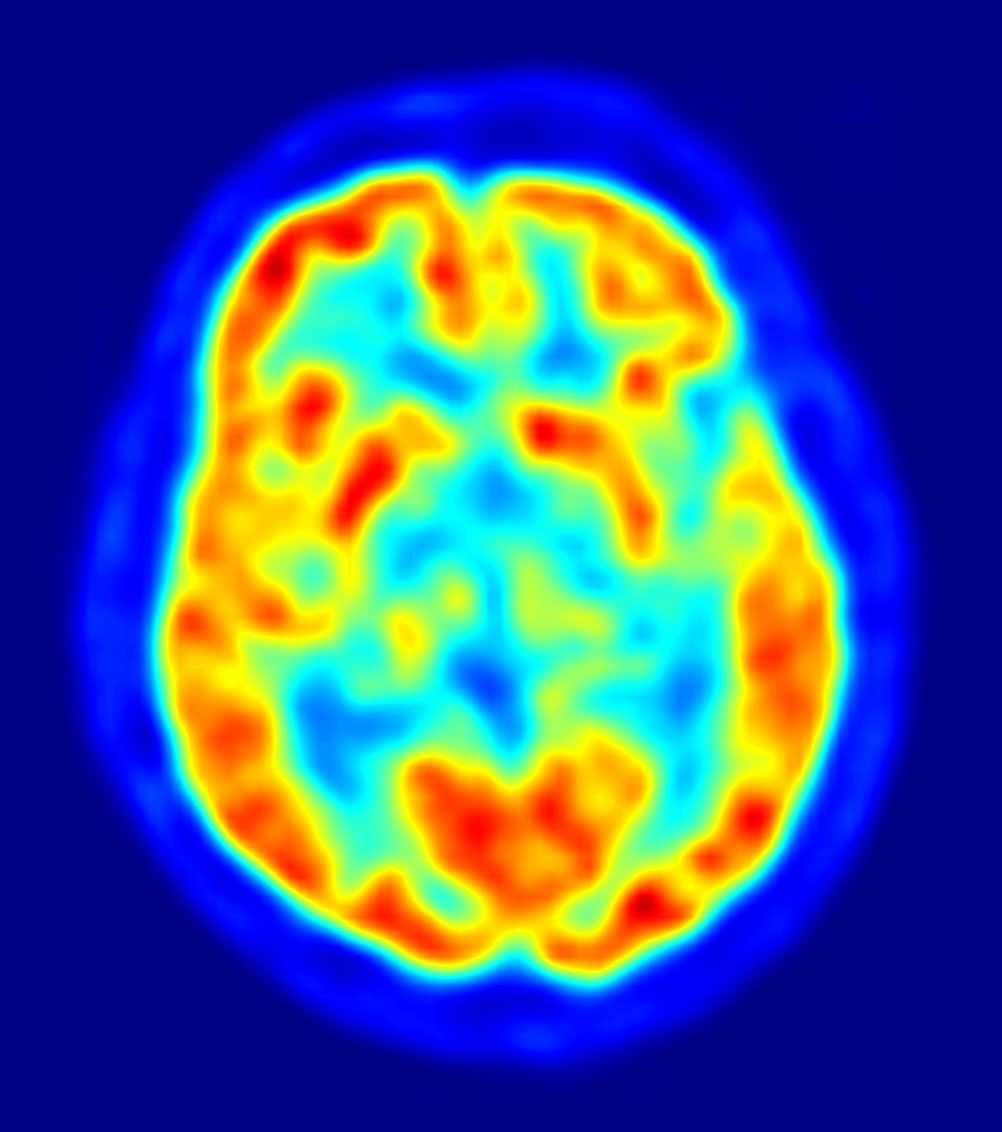

PET-image

Where culture shines a spotlight on an issue science can elaborate and I’ll finish with an observation on a study from 2006: Positron Emission Tomography was used to measure regional cerebral blood flow (rCBF) during clitoral stimulation and female orgasm. The team discovered that “deactivation of the temporal lobe is directly related to high sexual arousal.” [18]

The temporal lobe, one of the four main lobes of the cerebral cortex, is responsible for primary organisation of sensory output and damage can have a dramatic effect on an individual’s personality and even change it entirely: memories can be lost and languages can change. If every time a woman has an orgasm she enters a trope or allegorical state of the end of the self as she knows it, then with every orgasm she is indeed experiencing a Little Death.